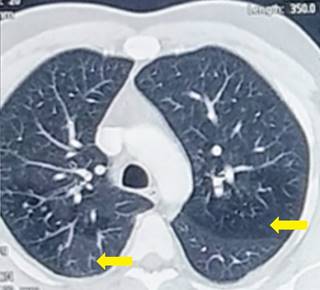

Los hallazgos de la TAC de tórax (Figuras 6-8) correspondieron a la presencia de imagen nodular irregular parahiliar derecha con hiperinflación segmentaria distal a la alteración. Se realizó fibrobroncoscopia para exploración de la vía aérea, la cual fue normal. Se dio egreso de la consulta de Neumología sin indicación quirúrgica debido a la ausencia de síntomas e infección respiratoria recurrente.

Figura 8: Tomografía de tórax-plano axial. El círculo rojo enmarca una región hipodensa en el lóbulo superior derecho. La flecha evidencia el mucocele del bronquio atrésico.